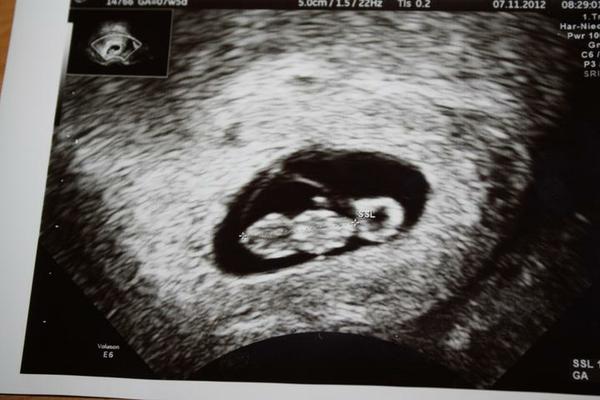

@luk25 - v osmom tehotenskom tyzdni zacina preberat funkciu placenta, ale nie plnne, to az v dvanastom tyzdni, j to postupny proces. Dovtedy je zivene cez zlte teliesko, co je aj dobre vidno na ultrazvuku pri babu, toto je nase prdolatko tyzden dozadu, to na pravo je ten zltkovy vak, ktory ho aktualne vyzivuje...